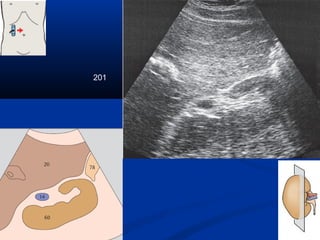

201